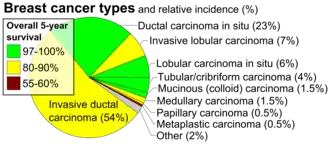

Invasive lobular carcinoma (ILC) is breast cancer arising from the lobules of the mammary glands.[1] It accounts for 5–10% of invasive breast cancer.[2][3] Rare cases of this carcinoma have been diagnosed in men (see male breast cancer).[4]